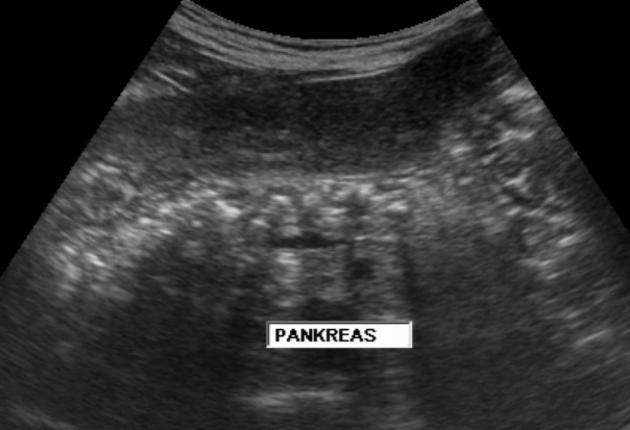

1. kép:

Hasnyálmirigy (pancreas)

Ezen az ábrán a hasnyálmirigy elhelyezkedését, az ultrahangos képét valamint egyes részeit láthatjuk.